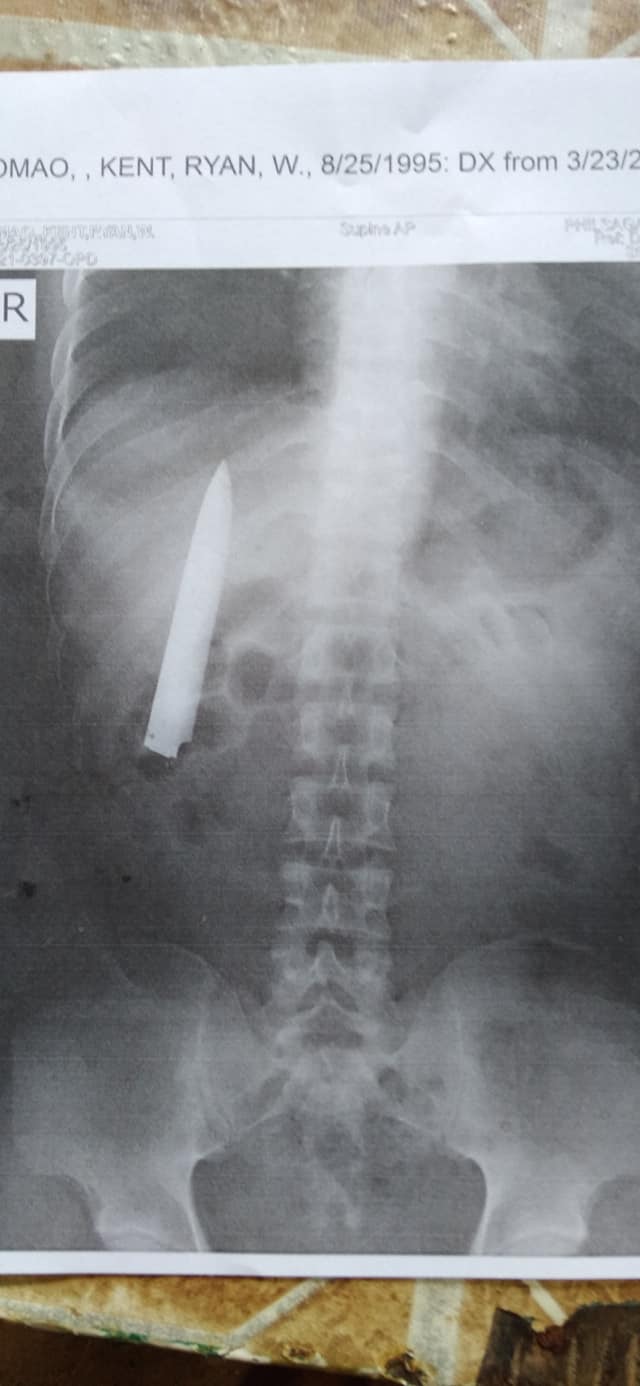

หนุ่มชาวฟิลิปปินส์ วัย 25 ปี ถูกแทงบาดเจ็บ ผ่านไปนาน 1 ปีกว่า เพิ่งรู้ มีดยาว 10 เซนติเมตร เข้าไปติดอยู่ในอก หลังเพิ่งได้เอกซเรย์ ห่างจากปอดนิดเดียว

มีสิ่งแปลกปลอมอยู่ในตัวโตเมียว เป็นชิ้นส่วนของมีดขนาดยาวประมาณ 10 เซนติเมตร ที่หลุดออกจากด้ามจับ เข้าไปติดอยู่บริเวณซี่โครงด้านขวาช่วงระหว่างอกกับหน้าท้อง ห่างจากจุดสำคัญนั่นก็คือปอด ไปเพียงนิดเดียว และผลเอกซเรย์นี้ทำให้เขาไม่ได้รับงานขุดเหมือง